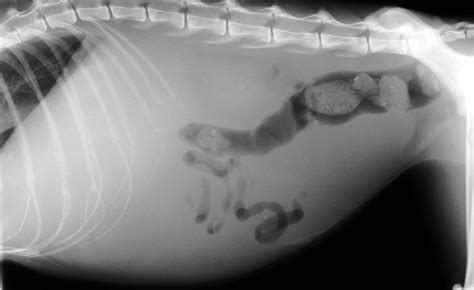

Awasome Cats Abdomen 2023. Before turning to more severe conditions, it is worth checking that your cat’s stomach isn’t swollen due to overeating or obesity. Five cats were presented to a veterinary teaching hospital with abdominal masses that could be felt during a routine exam. However, early nutritional support can help to lower the pain that your feline. They all had the classic signs of intestinal obstruction: Vomiting, diarrhea, weight loss, blood in vomit or stool, gas.